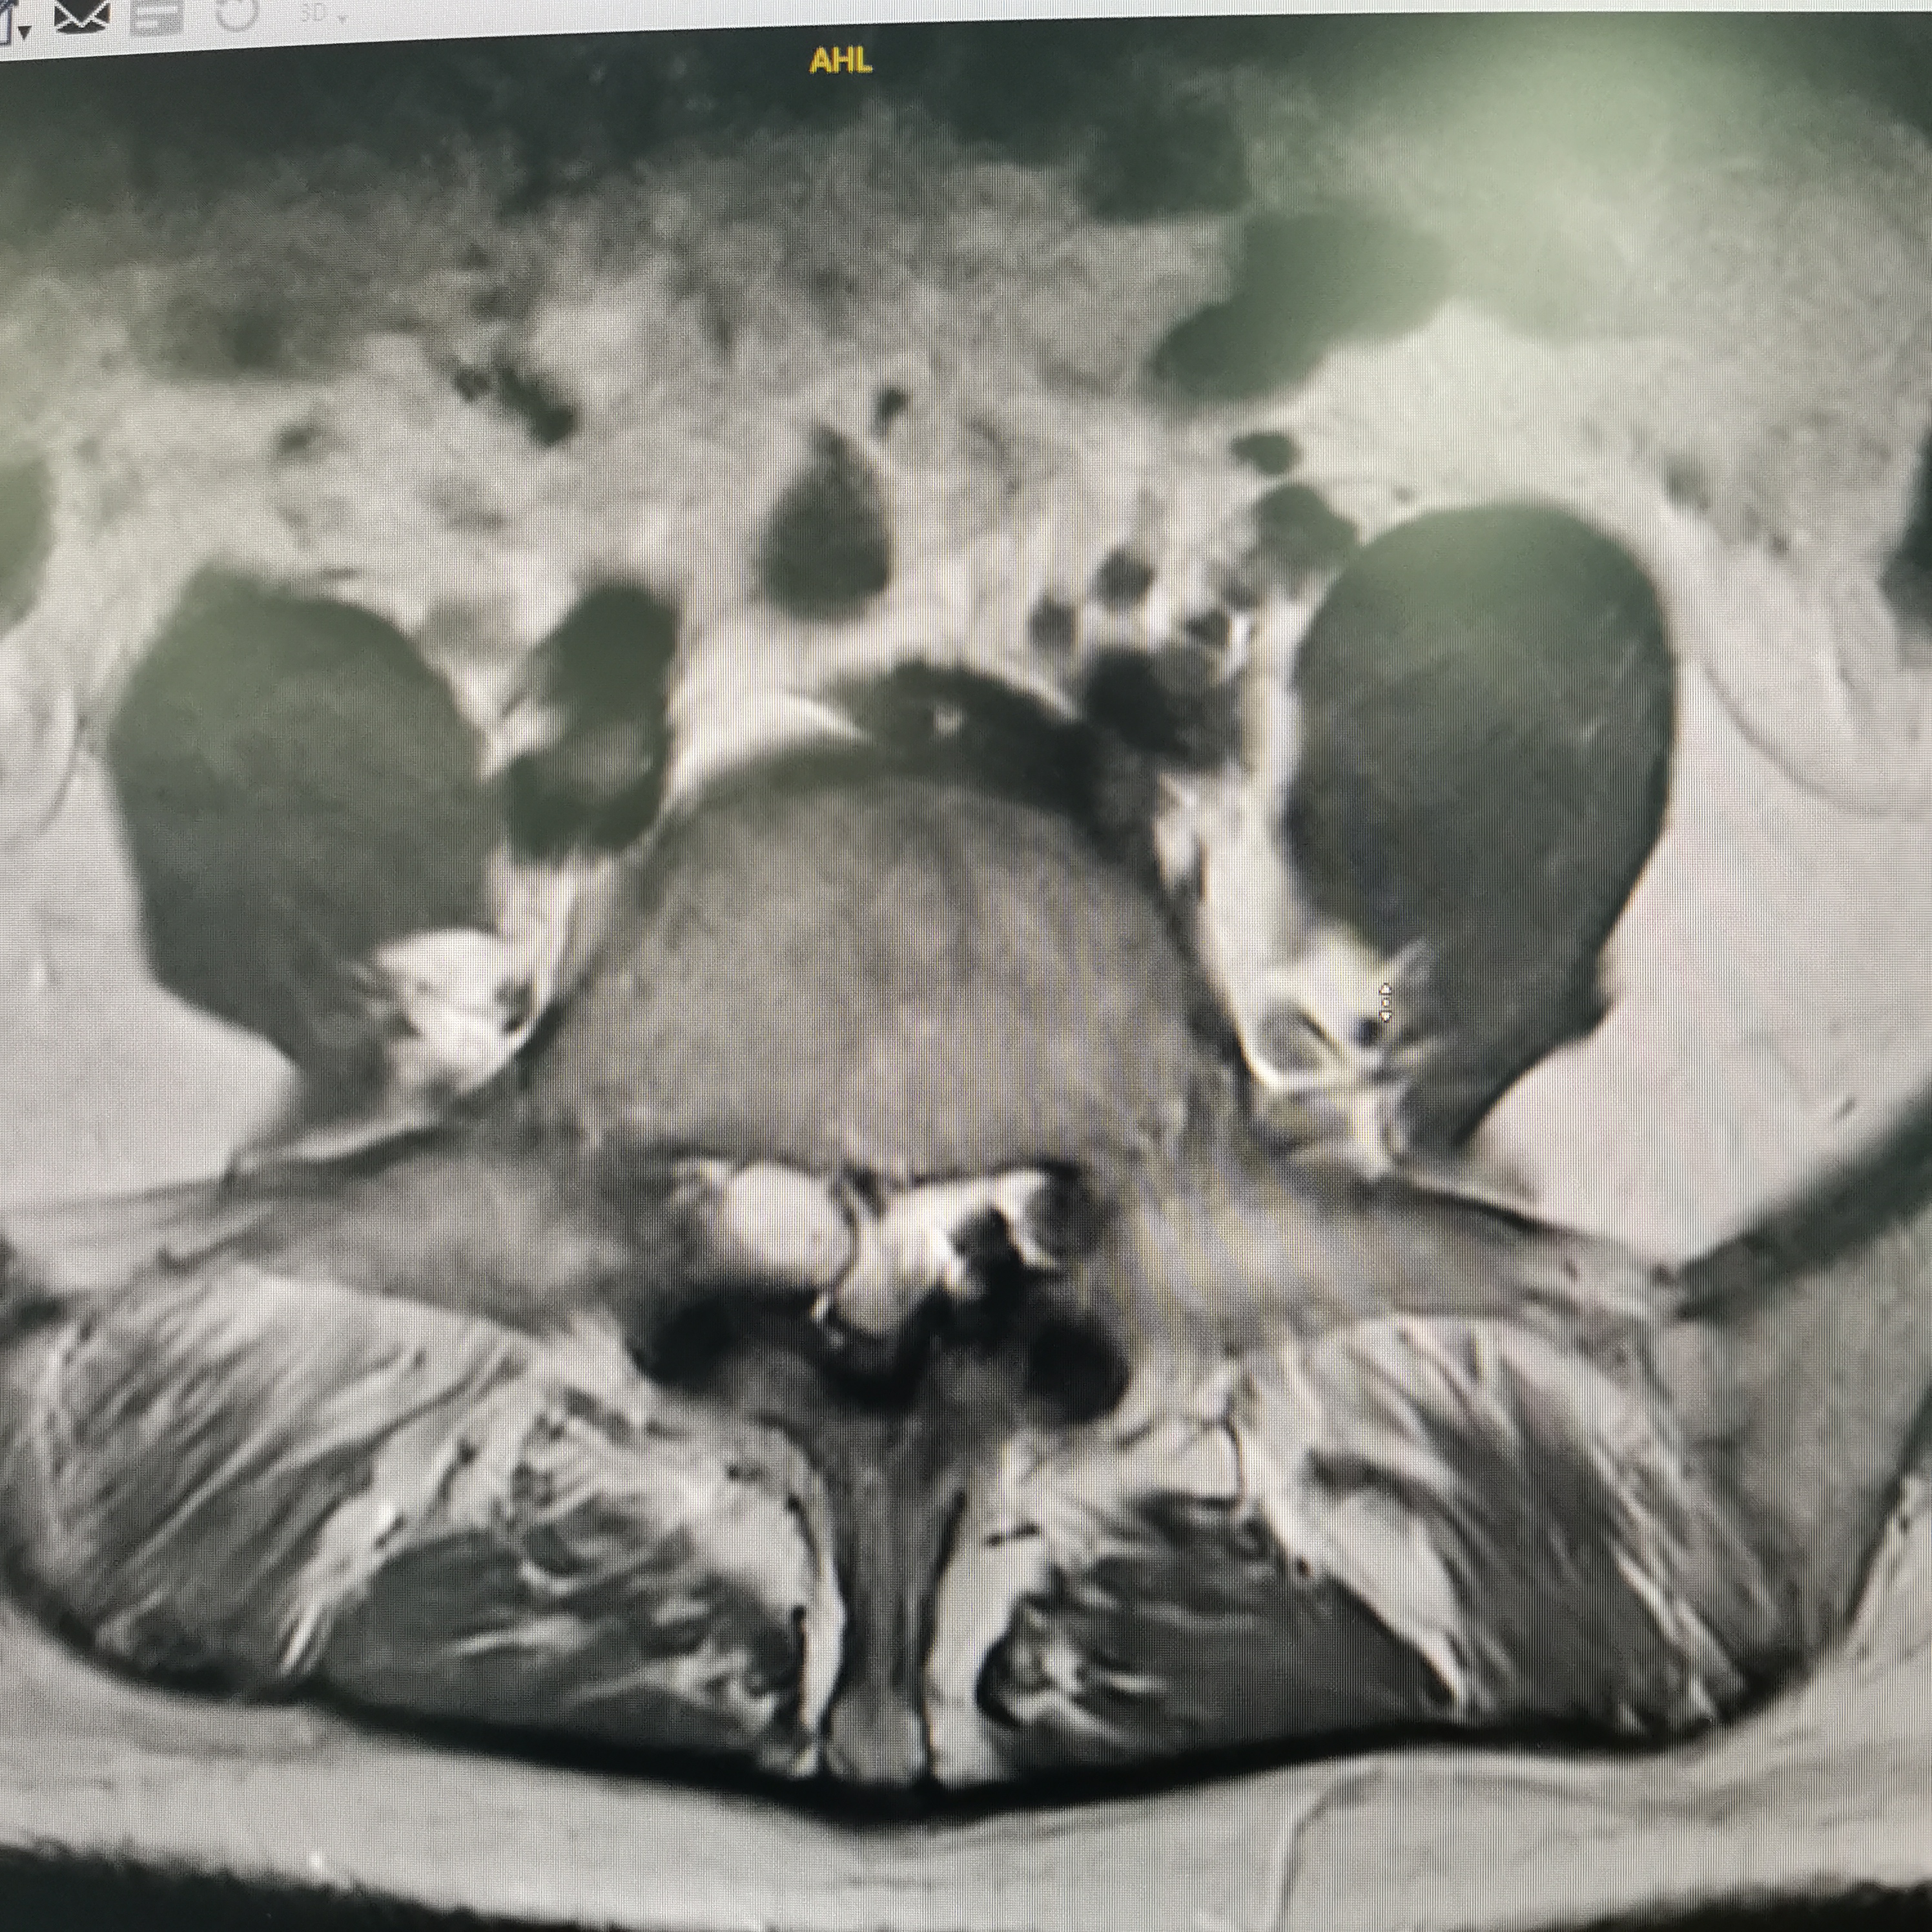

膝关节疼痛,原因是椎管内肿瘤,哑铃型生长,全切肿瘤,保留神经,疼痛症状消失…